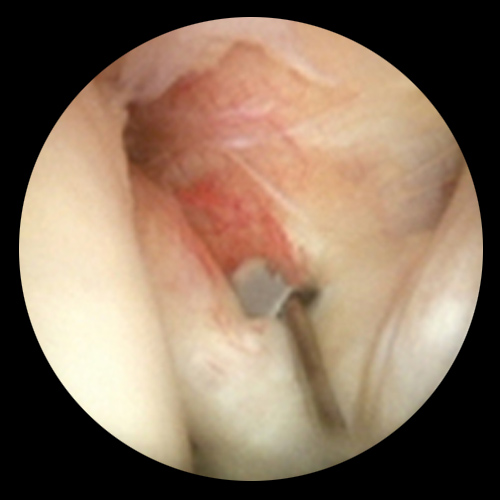

관절내시경은 작은 절개를 통해 초소형 카메라와 특수 기구를 관절 내부에 삽입하여 손상 부위를 직접 확인하고 치료하는 방법입니다.

어깨, 무릎, 발목 등 다양한 관절에 적용되며, 진단과 치료를 동시에 시행할 수 있는 최소침습 수술입니다.

차병원은 손상된 조직 부위를 정리하고, 만약 파열된 부분이 있다면 이를 봉합해주는 시술을 시행합니다.